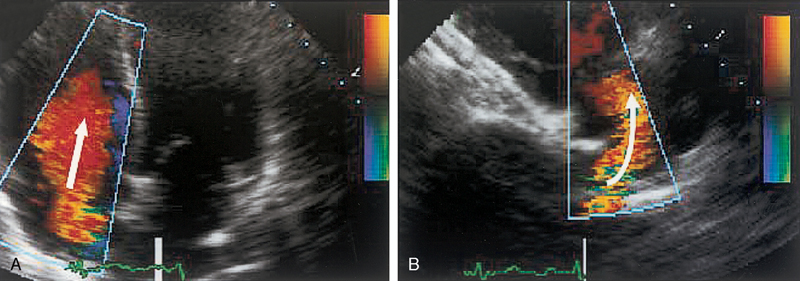

فحوصات تشخيصية لبعض امراض القلب والشرايين التاجية